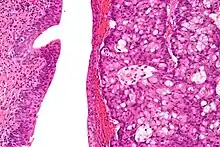

| Micrograph of urachal carcinoma (right of image) and non-malignant urothelium (left of image). H&E stain. | |

Histopathological Diagnosis

According to the current version (4th ed.) of the WHO classification of Tumours of the Urinary System, the diagnosis of a urachal adenocarcinoma usually needs a location of the tumor in the bladder dome and/or anterior wall, epicenter of the tumor in the bladder wall, absence of widespread cystitis cystica and/or cystitis glandularis beyond the dome or anterior wall, and absence of another similar structured tumor as a primary tumor elsewhere in the body. A urachal remnant in association with the tumor can help with the diagnosis.[10][11][12][13] In addition, other diagnostic systems also for urachal carcinomas that are not adenocarcinomas have been proposed.[14]

Immunohistochemical stains are usually less helpful in the histopathological differential diagnosis of urachal adenocarcinomas.[15]